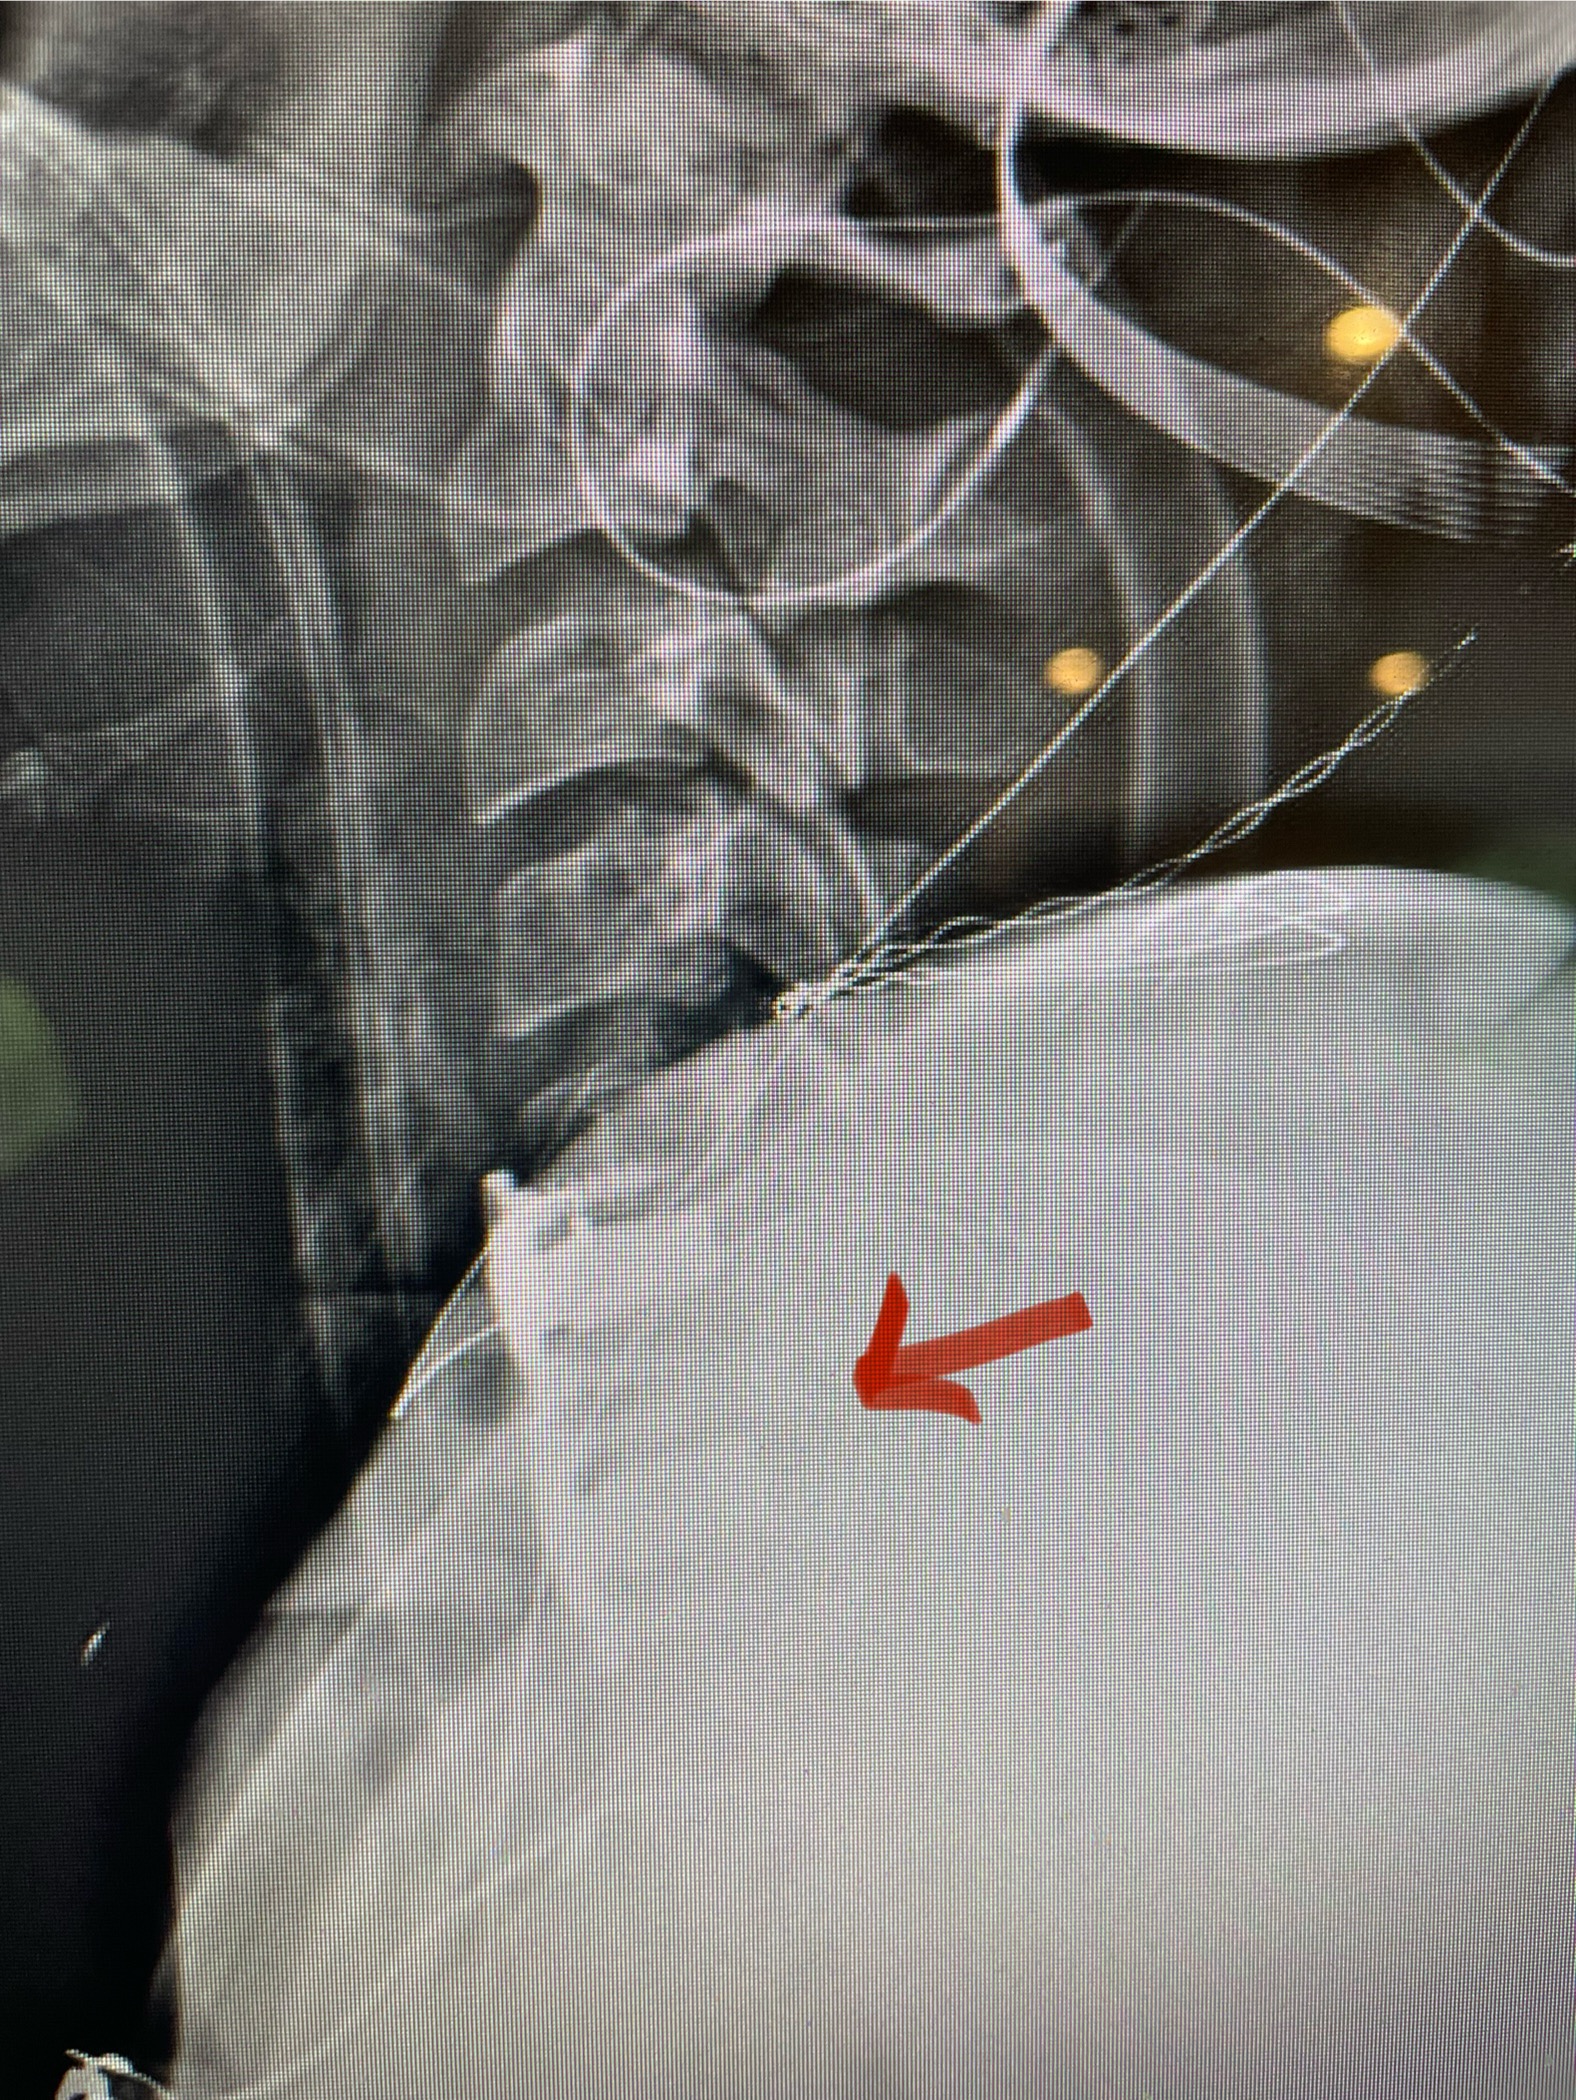

Clearly this explained her right upper extremity symptoms. Because of her weakness, it was decided to perform an anterior cervical discectomy at C5-6 and C6-7 and interbody fusion with plate. An extruded disc was found at C6-7. The patient did well postoperatively with improvement of her radiating pain and strength (Fig 3). This case illustrates the importance of repeating an MRI if the symptoms and signs do not correlate with the MRI findings. Disc herniations can change. They can be reabsorbed, and they can also worsen over time.

Fig 3: Intraoperative lateral cervical x-ray demonstrating good placement of the C5-C7 interbody cages and plate (red arrow)